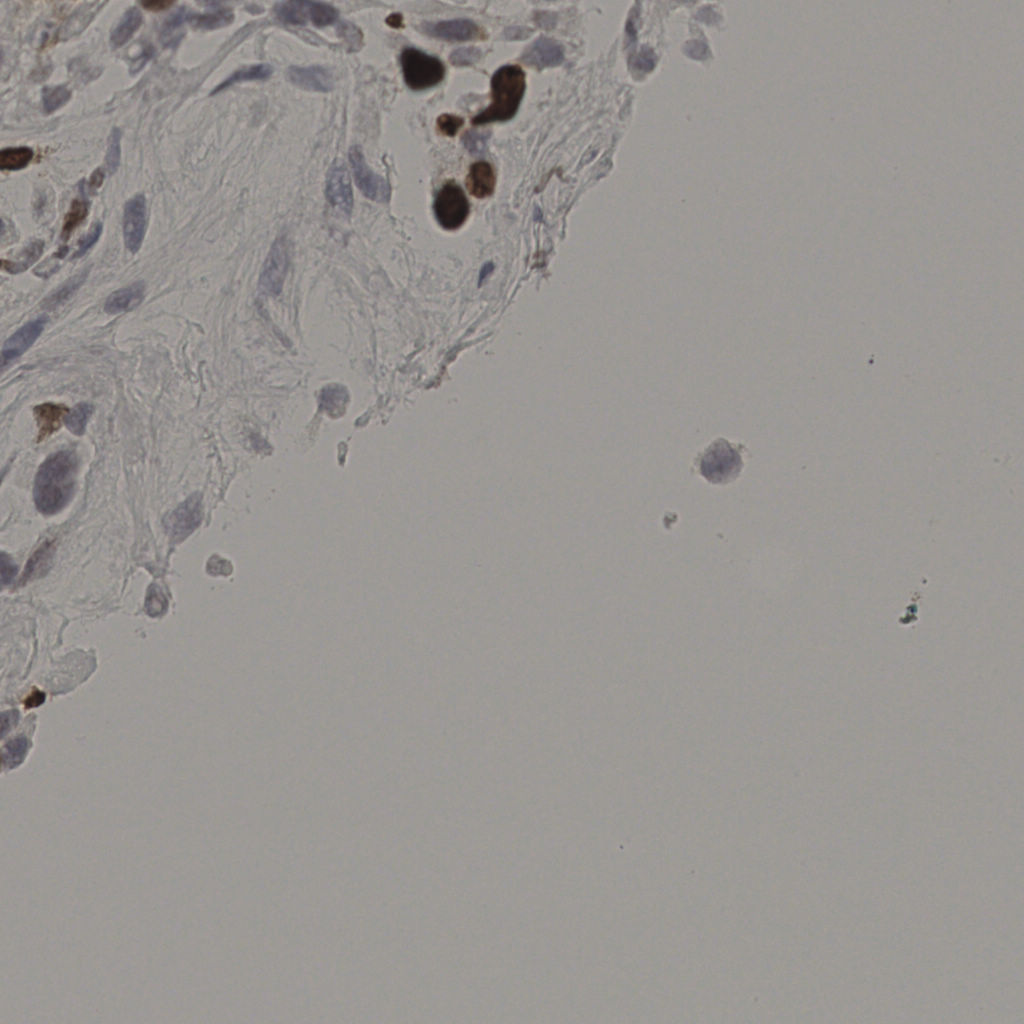

17.75%

Ki67 指数

阴 7986 阳 1723

20240285Ki-67.ndpi